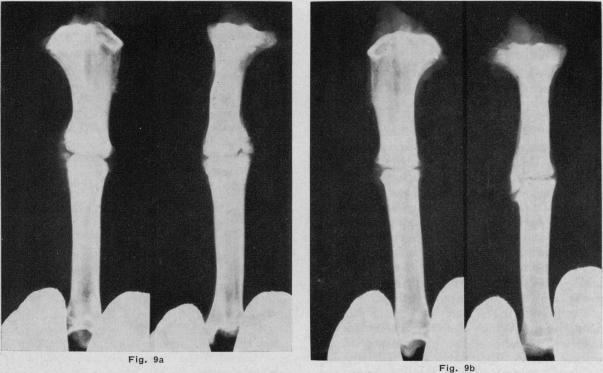

The effect of heat on the healing of fractures: a preliminary experimental report.

Can Med Assoc J. 1967 Aug 5;97(6):274-80.